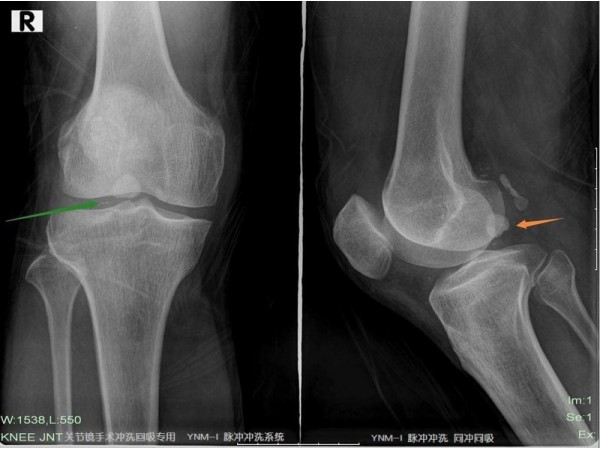

產(chǎn)品名:骨科一次性脈沖沖洗器YNM-I型

企業(yè)名:濟南盈諾醫(yī)用設(shè)備有限公司